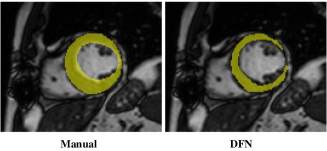

Refer to caption

(a) Epicardium

(b) Endocardium

Fig. 7: Comparison of (a) epicardium and (b) endocardium segmentation accuracies for different methods on LV-09 dataset in averaged 3D Dice metric (ADM). The ADM are averaged over all testing subjects. The red central mark of the box is the median and the edges are the 25th and 75th percentiles, while the red plus signs represent outliers.

Our DFN and DFN_NMI based on LF registration achieve lower values of “Good” percentage in all comparisons, due to the inaccurate registration results without using landmarks on this dataset. This indicates that our method, as a multi-atlas segmentation method, relies on a relatively good registration method, and breaks down on LV-09 dataset when LF registration does not work well. Figure 7 compares the segmentation accuracies in the box-plot, and Figure 8 shows the epicardium and endocardium segmentation results using different methods for the basal, mid-ventricular and apical slices from one subject in testing set.